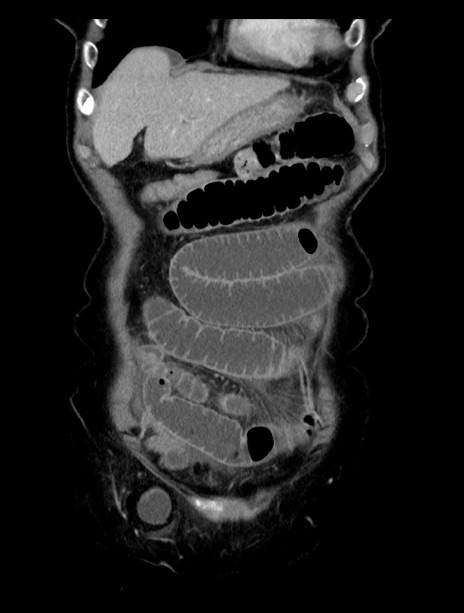

症例23(冠状断像)

【症例】70歳代女性

【主訴】下腹部痛・嘔吐

【現病歴】2日前より腹痛あり。昨日嘔吐あり。症状改善しないため来院。

【既往歴】胃GISTに対して胃部分切除後。

【身体所見】BT 37.1℃、BP 128/77mmHg、腹部:平坦・軟、下腹部に圧痛あり。

【データ】WBC 10200、CRP 0.31